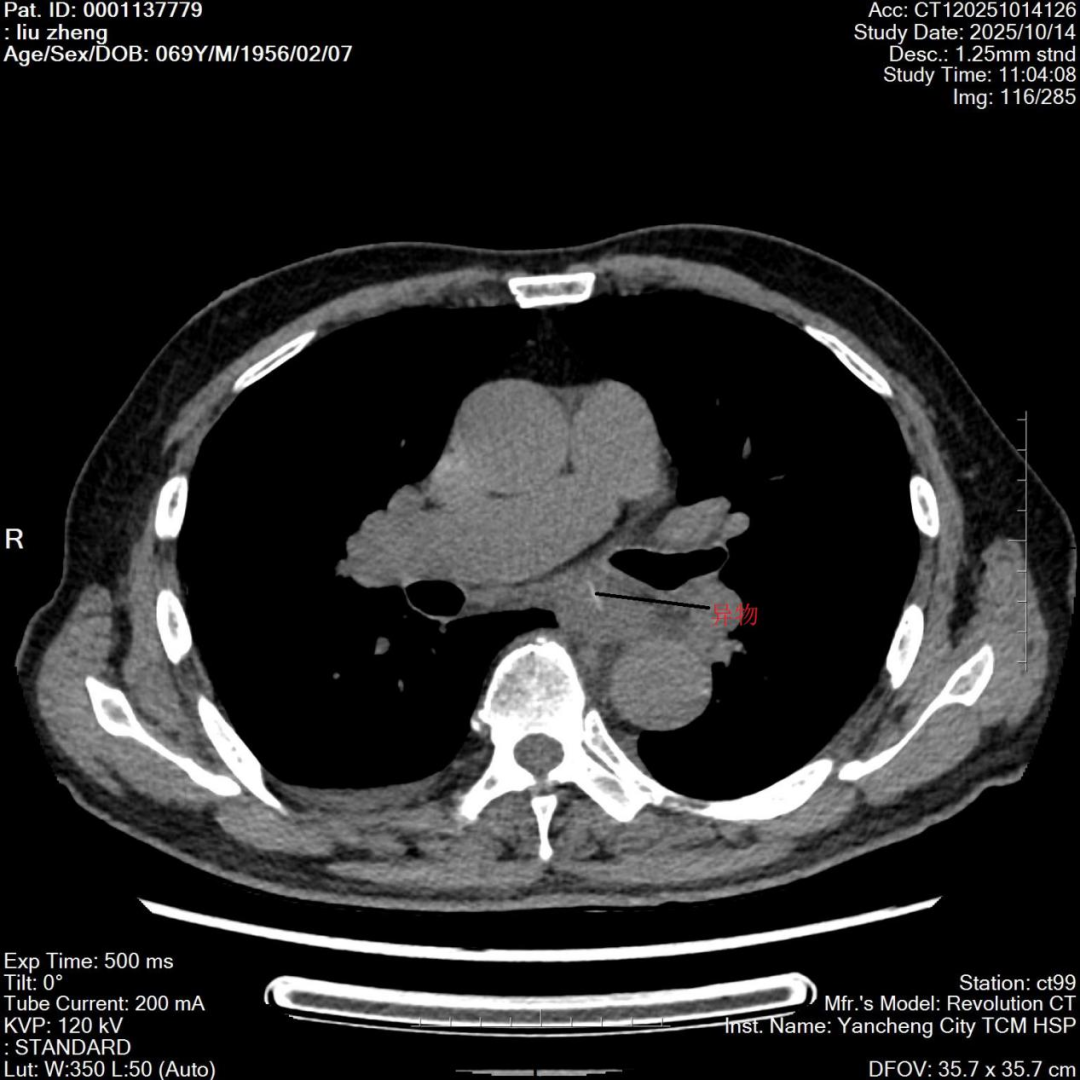

病人刘老伯(化名)进食鱼肉后胸骨后疼痛,发热二日余来我院检查。CT显示:患者食管中下段有鱼骨样异物,经过多学科讨论,考虑鱼刺周围目前无大血管,可尝试胃镜下取出,如出现困难,则胸外科接手进行手术治疗,手术非常顺利,鱼刺异物成功取出。经过精心治疗,病人体温逐渐降低,住院五天后复查食管周围水肿明显好转,经过医疗及护理团队精心治疗护理,刘老伯住院二周后正常进食,康复出院。

患者影像资料